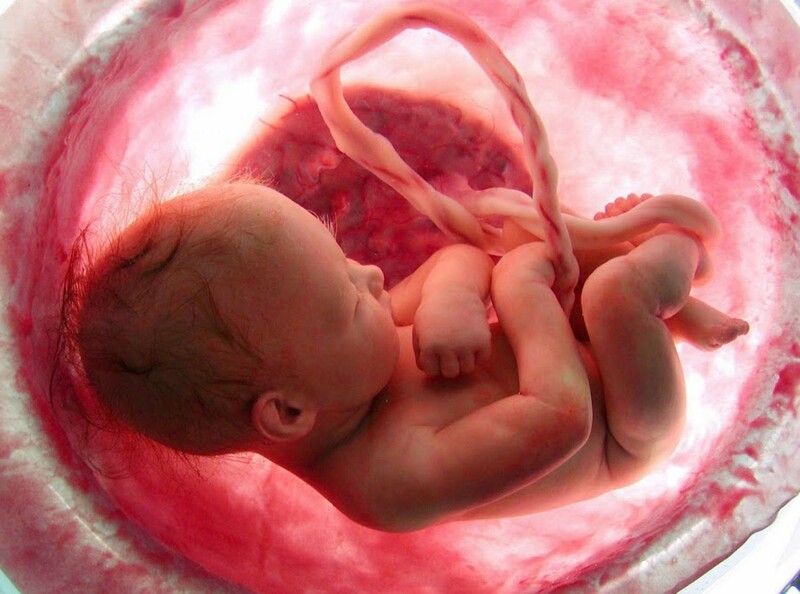

Mang thai là một hành trình kỳ diệu, tràn đầy sự chờ đợi và niềm vui đối với những người đang chuẩn bị làm cha mẹ. Thông qua phương pháp siêu âm, cha mẹ có thể kết nối gần hơn với bé yêu cũng như chứng kiến sự phát triển của bé qua từng giai đoạn. Tuy nhiên, tần suất siêu âm thai luôn là chủ đề được nhiều bà mẹ tương lai quan tâm.

Lần siêu âm đầu tiên được tiến hành ngay sau khi xác nhận có thai, mục đích nhằm đánh giá thai nhi trong bụng mẹ có phát triển đúng vị trí không, thai được bao tuần, kiểm tra lượng nước ối, tình trạng của nhau thai,... Tuy nhiên trên thực tế, nhiều chị em lần đầu mang thai có tâm lý nôn nóng, tò mò về sự phát triển của con mình nên muốn được siêu âm nhiều lần, thường xuyên trong suốt thai kỳ.